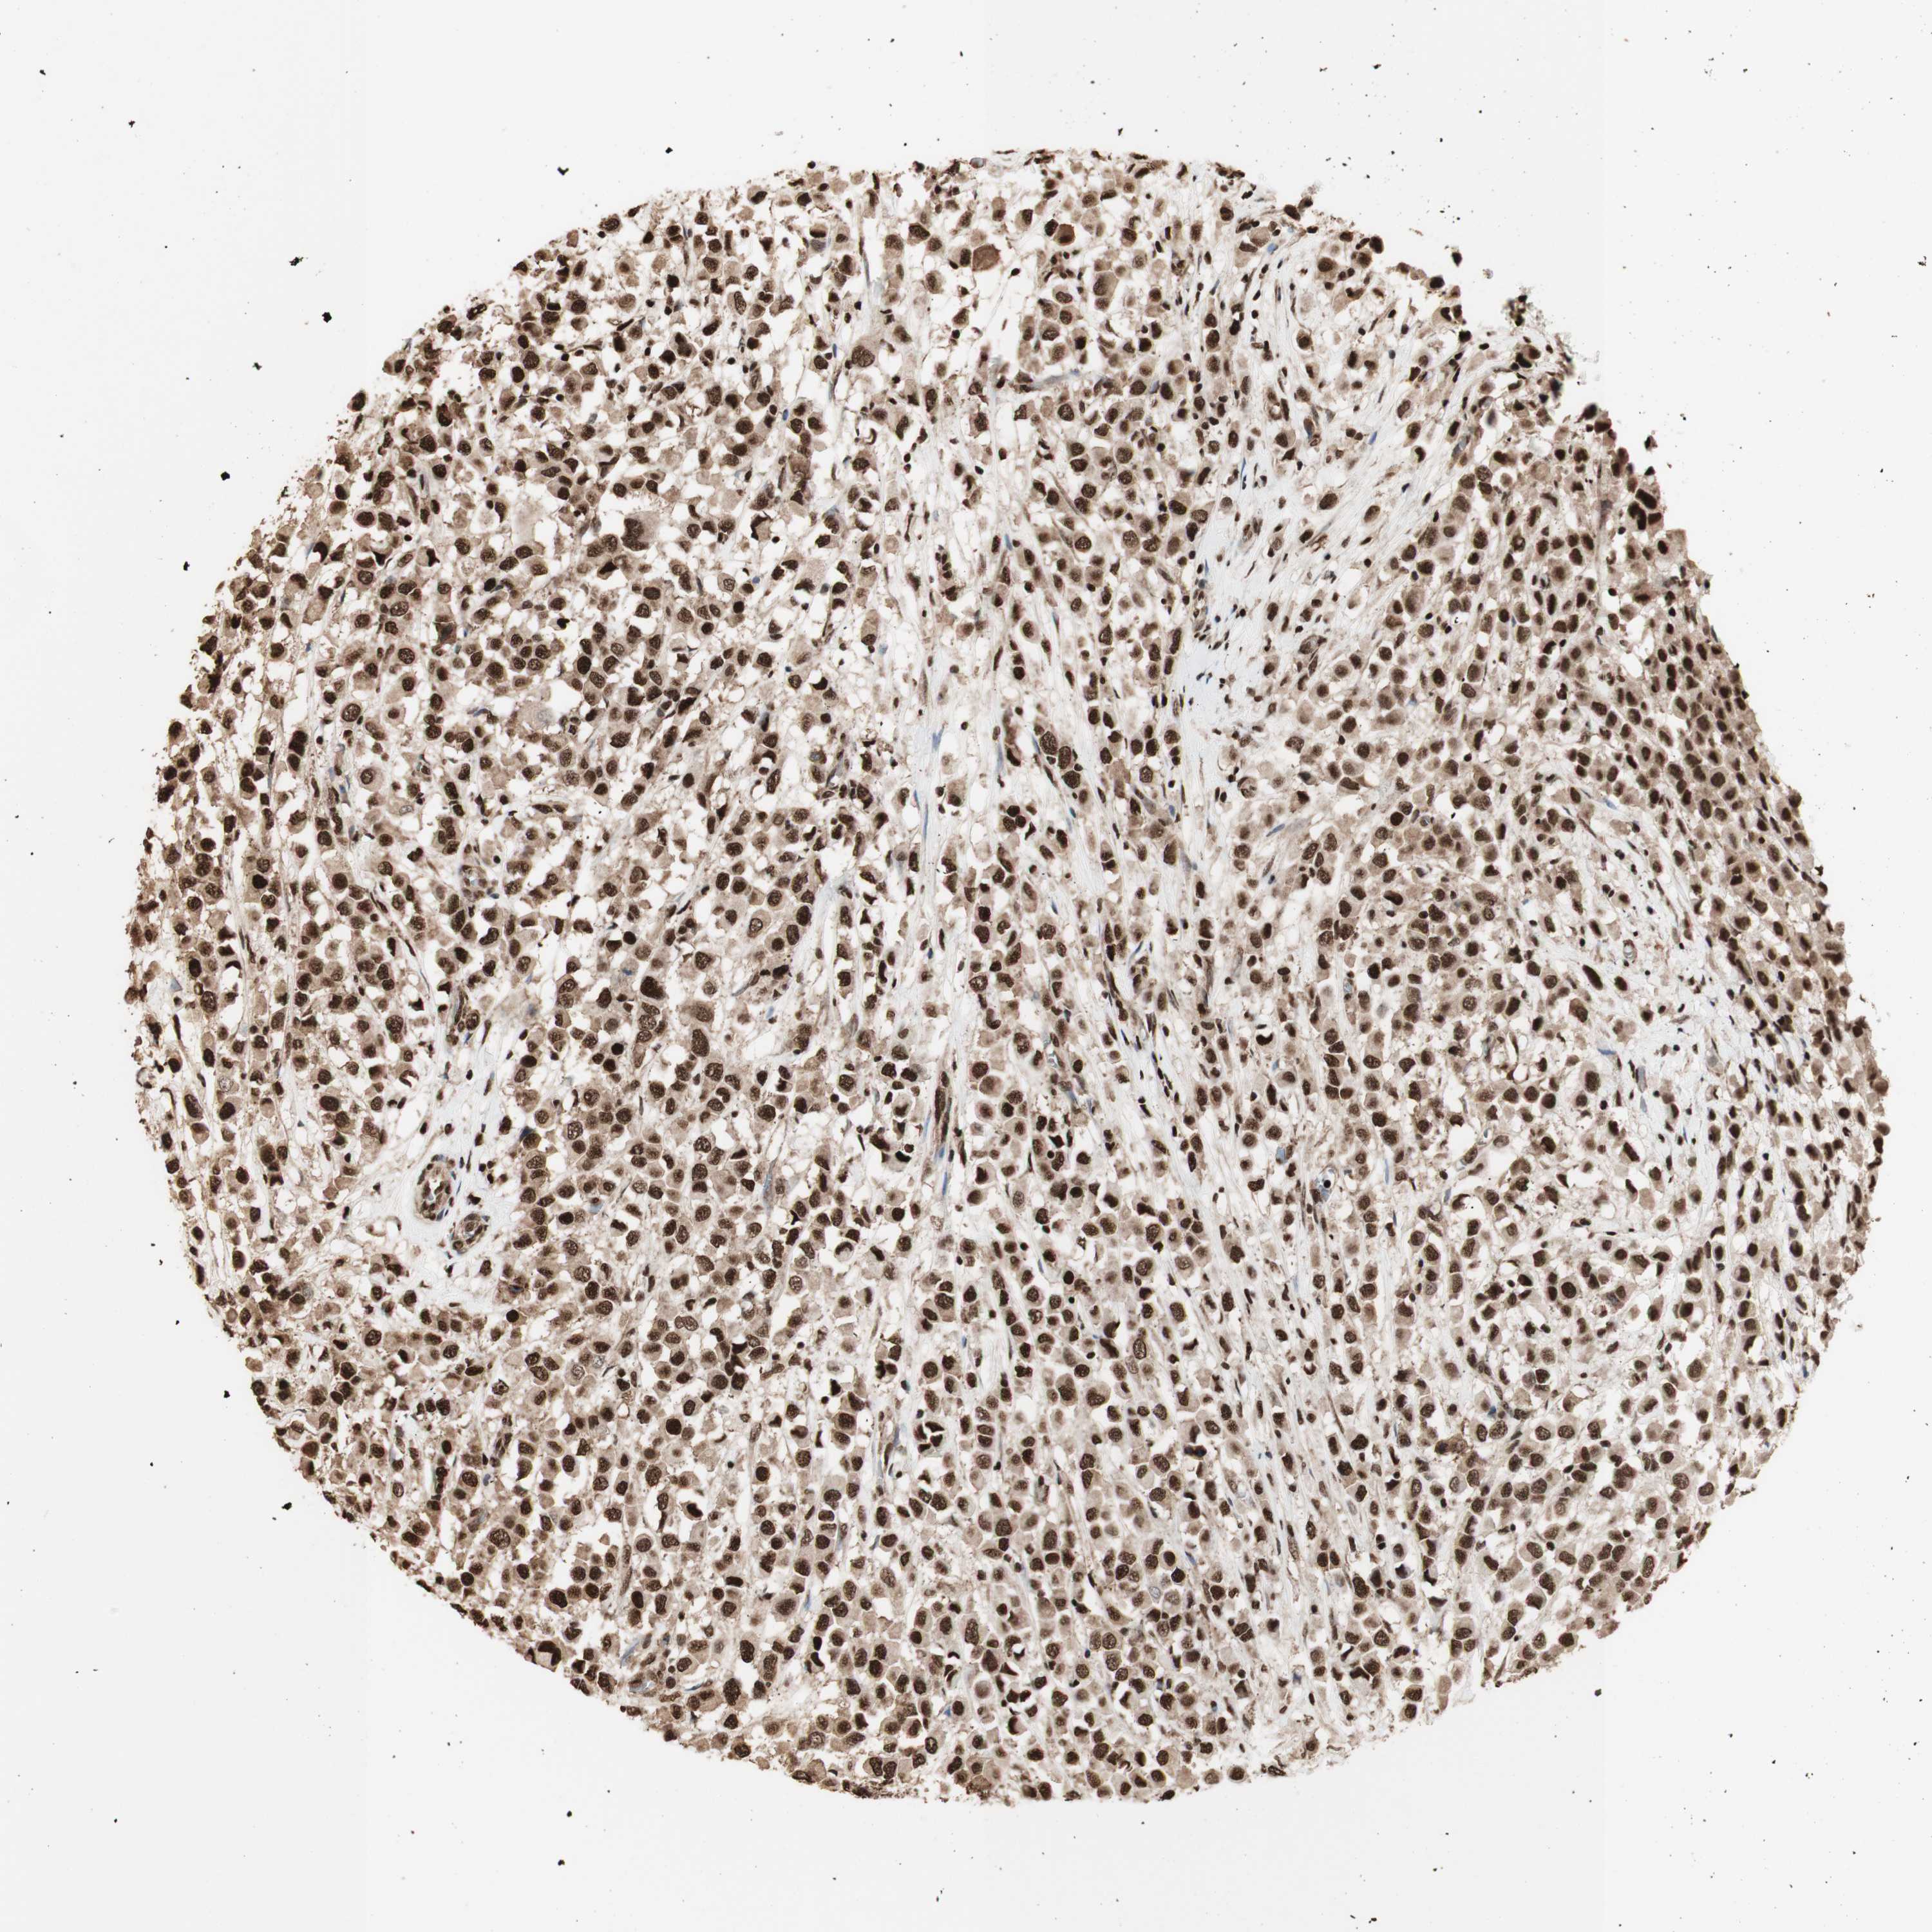

BRCA TCGA BRCA VALIDATION PROTEIN EXPRESSION